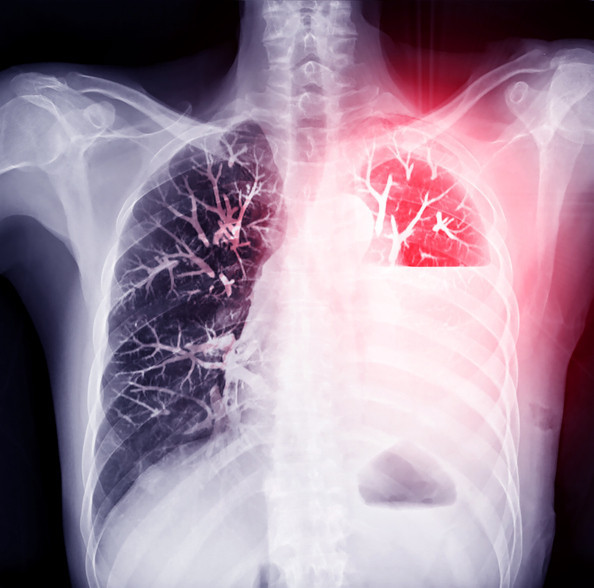

Akciğerin etrafını saran ve “plevra” olarak adlandırılan zar yapıları arasına hava kaçması sonucu akciğerin kısmen veya tamamen sönmesi durumu “pnömotoraks” olarak tanımlanıyor. Normalde akciğer ile göğüs duvarı arasında hava bulunmuyor.

Akciğerin yüzeyinden herhangi bir nedenle bu aralığa hava geçmeye başlarsa, her nefes almamızla burada biriken hava akciğere baskı yaparak, kısmen veya tamamen sönmesine neden oluyor. Akciğer sönmesinde en tipik başlangıç, ani başlayan ve tek taraflı göğüs ağrısı ile nefes darlığı oluyor.

Pnömotoraks tanısı; muayene bulguları, akciğer grafisi veya bazı durumlarda tomografi ile konuluyor. Tedavide amaç, göğüs boşluğu içinde biriken havanın boşaltılarak akciğerlerin yeniden şişmelerini sağlamak. Tedavi akciğerin ne kadar çöktüğüne ve hastanın genel durumuna göre planlanıyor.